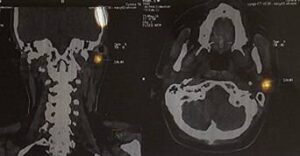

За 12 місяців 2024 року виконано 198 оперативних втручань з приводу меланоми, з них 88 операцій — біопсія сигнального лімфатичного вузла.

За 9 місяців 2025 року проведено 168 операцій з приводу меланоми, у тому числі 91 оперативне втручання із біопсією сигнального лімфатичного вузла.

У 2024 році було виявлено 174 пацієнти з меланомою, з яких 120 — на І–ІІ стадіях захворювання, а 34 — на занедбаних ІІІ–IV стадіях. Спеціалізоване лікування отримали 92,5% пацієнтів, що становить 161 особу.

За 9 місяців 2025 року зареєстровано 140 нових випадків меланоми: 100 пацієнтів — на І–ІІ стадіях та 24 — на ІІІ–IV стадіях. Спеціалізоване лікування отримали 92% пацієнтів (129 осіб).

Станом на вересень 2025 року на обліку у Львівській області перебуває 2249 пацієнтів із меланомою, з яких 1483 особи знаходяться під наглядом понад 5 років.